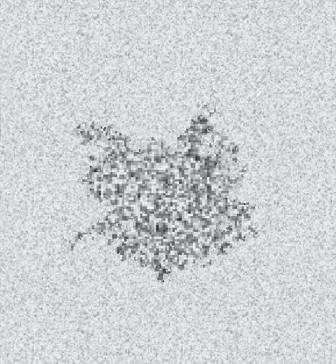

Most echoes in the body do not arise from specular reflectors but rather from much smaller interfaces within solid organs. In this case the acoustic interfaces involve structures with individual dimensions much smaller than the wavelength of the incident sound. The echoes from these interfaces are scattered in all directions. Such reflectors are called diffuse reflectors and account for the echoes that form the characteristic echo patterns seen in solid organs and tissues (see Fig. 1.5B). The constructive and destructive interference of sound scattered by diffuse reflectors results in the production of ultrasound speckle, a feature of tissue texture of sonograms of solid organs (Fig. 1.6). For some diagnostic applications, the nature of the reflecting structures creates important conflicts. For example, most vessel walls behave as specular reflectors that require insonation at a 90-degree angle for best imaging, whereas Doppler imaging requires an angle of less than 90 degrees between the sound beam and the vessel.

FIG. 1.6 Ultrasound Speckle. Close inspection of an ultrasound image of the breast containing a small cyst reveals it to be composed of numerous areas of varying intensity (speckle). Speckle results from the constructive (red) and destructive (green) interaction of the acoustic fields (yellow rings) generated by the scattering of ultrasound from small tissue reflectors. This interference pattern gives ultrasound images their characteristic grainy appearance and may reduce contrast. Ultrasound speckle is the basis of the texture displayed in ultrasound images of solid tissues.

Spatial Compounding

An important source of image degradation and loss of contrast is ultrasound speckle. Speckle results from the constructive and destructive interaction of the acoustic fields generated by the scattering of ultrasound from small tissue reflectors. This interference pattern gives ultrasound images their characteristic grainy appearance (see Fig. 1.6), reducing contrast (Fig. 1.18) and making the identification of subtle features more difficult. By summing images from different scanning angles through spatial compounding (Fig. 1.19), significant improvement in the contrast-to-noise ratio can be achieved (Fig. 1.20). This is because speckle is random, and the generation of an image by compounding will reduce speckle noise because only the signal is reinforced. In addition, spatial compounding may reduce artifacts that result when an ultrasound beam strikes a specular reflector at an angle

FIG. 1.18 Effect of Speckle on Contrast. (A)

Speckle noise partially obscures the simulated lesion. (B) The speckle has been reduced, increasing contrast resolution between the lesion and the background. (With permission from Merritt CR. Technology update. Radiol Clin North Am. 2001;39:385-397.7)